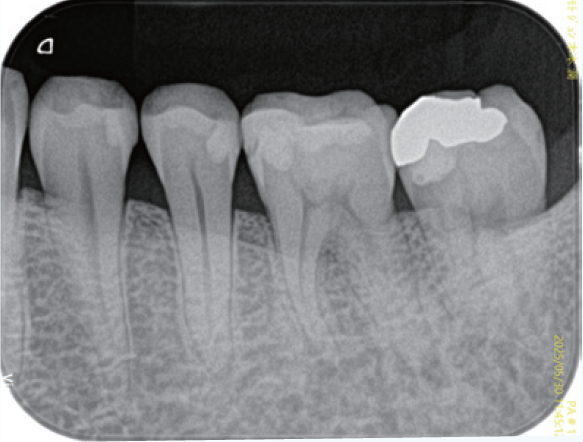

症例1は、根管処置後の打診痛を主訴に来院された症例である。

初診時のデンタルX線像を示す。レントゲン所見では根尖周囲組織に炎症を示す像を認め、その影響が上顎洞粘膜の肥厚の原因と推測されるレントゲン像である。

<症例1>●初診時年齢 31歳 女性 初診日2011/10/14

左上5番を他院で根管充填後、打診痛が消失しないので転院され受診患歯にはインレー修復がされている。根尖部は上顎洞と近接しており、上顎洞粘膜の肥厚も認められた

(症例1・①)根管充填の状態は比較的良好である。根管拡大・形成の3次元的評価のためCBCTを撮影。

CT像左上5番根尖部を中心として上顎洞粘膜の肥厚が認められ、根尖性歯周組織炎の影響が上顎洞まで及んでいると考えられた

根管処置後の修復が保存修復されて髄室開拡に制限があり、歯頸部周辺に存在する頬口蓋側に広がる髄角の形態が確認でき(症例1・②)、この部分に根管拡大不足の可能性を疑えた。根尖病変の原因として、頬口蓋的な根管拡大不足による起炎物質の取り残しによる感染が要因の一つであると診断した。より的確な予防形成を行うにあたり、器具操作の向上のため髄室開拡の修正が必要であると判断した。よって最終修復は歯冠修復による補綴修復が必要であると患者に説明し、承諾が得られたので再治療を行なった。

(症例1・②)

線で示した部分に髄角部の形態がそのまま残存していることが予測され拡大不足、未処置部分が存在すると判断した

根管充填後のレントゲン所見を示す(症例1・③)。術前と比較し、レントゲン上では上顎洞粘膜の肥厚も改善傾向が認められる。根尖病変の主原因がバイオフィルムであり、機械的な拡大形成は必須であるため根管を3次元的に捉えて処置することが重要である。デンタルX線では近遠心的な形態は確認することができるが、頬舌的な形態を確認することは偏心投影をしても難しい。CBCTは根管処置を行う上で非常に有益な情報を得ることができると考える(症例1・④、⑤)。

(症例1・③)

根管充填、支台築造後のレントゲン像術前と比較しレントゲン上では上顎洞粘膜の肥厚も改善傾向が認められる

(症例1・④)

術前と比較して頬口蓋方向に膨らんでいた髄角部の形態の変化が確認でき、未処置部分が減少していることが確認できる。上顎洞粘膜の肥厚も術前と比較し改善傾向にある

(症例1・⑤)根尖部のCBCT像

根尖部の開口部は3つ以上存在し、根管充填材が開口部を封鎖していることが確認できる